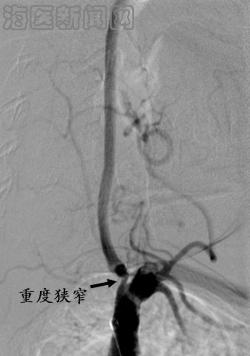

病例1 黄某某,女,70岁,因为“头晕伴呕吐半月”入院,既往有糖尿病病史。术前不能头晕下床,造影发现左侧椎动脉开口重度狭窄,予以支架置入术,血管再通。已随访2年6月,目前无头晕症状,能出国旅游。

治疗之前,左侧椎动脉重度狭窄 治疗之后,左侧椎动脉完全开通